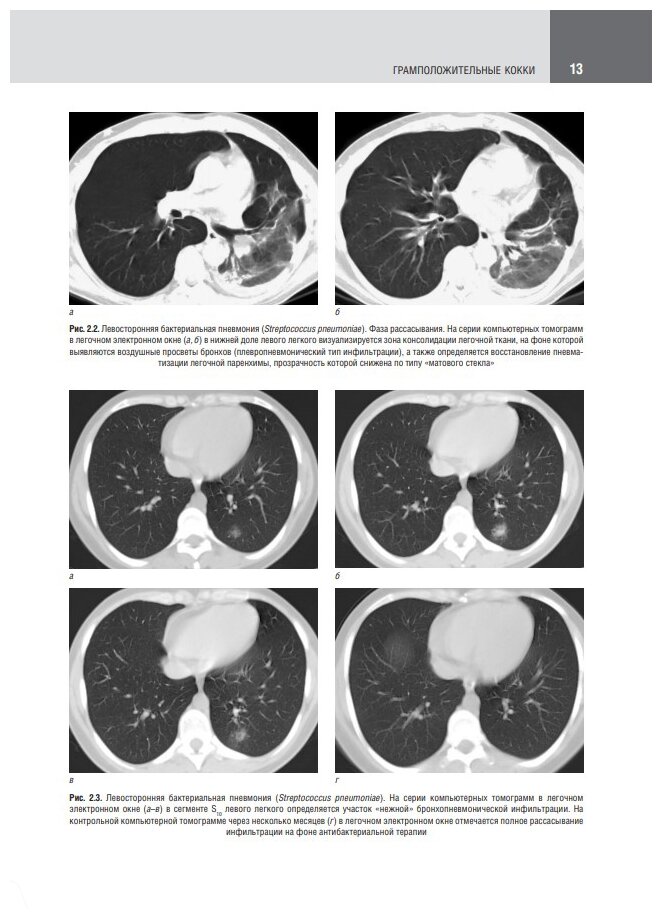

Атлас посвящен использованию рентгеновской компьютерной томографии в диагностике различных инфекционных заболеваний легких. В настоящее время общепризнана ведущая роль этого метода лучевой диагностики не только при первичном обследовании пациентов с подозрением на данные заболевания, но и в процессе лечения и динамического наблюдения в качестве метода контроля. Представлены изображения и комментарии к ним, которые могут использоваться врачами-рентгенологами при написании заключений.

В отдельной главе рассмотрены конкретные клинические примеры компьютерной томографии в диагностике пневмоний, вызванных новой коронавирусной инфекцией COVID-19. Подчеркивается ведущая роль этого метода исследования в определении степени изменений и вероятности наличия данного типа вирусной пневмонии. Проиллюстрированы возможности компьютерной томографии в динамическом наблюдении при благоприятном или неблагоприятном течении патологического процесса, а также в выявлении различных осложнений.